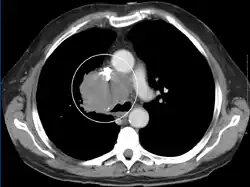

La technique d'imagerie la plus utile est la tomodensitométrie avec injection de produit de contraste iodé, qui permet de visualiser le réseau veineux et d'identifier la cause de la compression[2]. En cas de contre-indication au scanner, une IRM peut être réalisée[4].